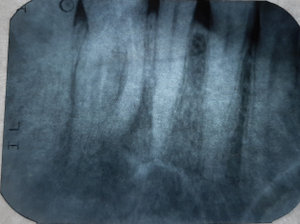

После удаления нерва из зуба, кажется четырнадцатый, на верхней челюсти, проткнули на 2 сантиметра дальше корня, я показался другому врачу и он говорит, что теперь нужно удалять зуб.

Неужели ничего нельзя поделать, чтобы сохранить зуб? Чем-то запломбировать этот канал? Мне 66 лет, их, зубов, уже почти не осталось.

В принципе, доктор прав, также возможно провести хирургическую манипуляцию (резекция верхушки корня).